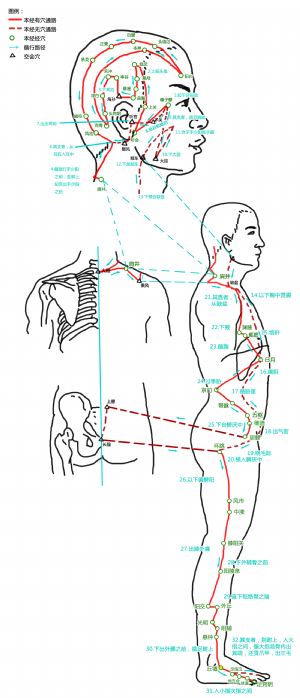

丘墟爲經穴名(Qiūxū GB40)[1]。出《黃帝內經靈樞·本輸》。屬足少陽膽經[1][2]。丘墟是足少陽膽經的原穴[2][2][3]。丘即土丘,墟指山下之地,此穴在外踝前下方,外踝突起如丘,故名丘墟[3]。丘墟穴主治頭項、肝膽、腰腿等疾患:如偏頭痛,目疾,齒痛,耳聾,咽腫,項強,腋腫,瘰癘,氣喘,胸脅痛,腰膝痛,腳跗腫,足跟痛,寒熱往來,渾身瘙癢,瘧疾,疝氣,頸項痛,胸脅脹痛,下肢痿痹,外踝腫痛,腳氣,現代又多用丘墟穴治療血管性頭痛,神經性耳聾,胸膜炎,膽囊炎,腋窩淋巴結炎,肋間神經痛,腓腸肌痙攣,腸疝痛,坐骨神經痛,踝關節及其周圍軟組織炎,胸脅滿痛,頸項強,腋下腫,膽絞痛,腋下淋巴結炎等。

8 丘墟穴的定位

標準定位:丘墟穴在足外踝的前下方,當趾長伸肌腱的外側凹陷處。足少陽膽經的原穴[5]。

丘墟穴位於足外踝前下方,當趾長伸肌腱的外側凹陷處。伸足取之[5]。

丘墟穴位於足背外側,外踝前下緣,當趾長伸肌腱外側凹陷處[5]。